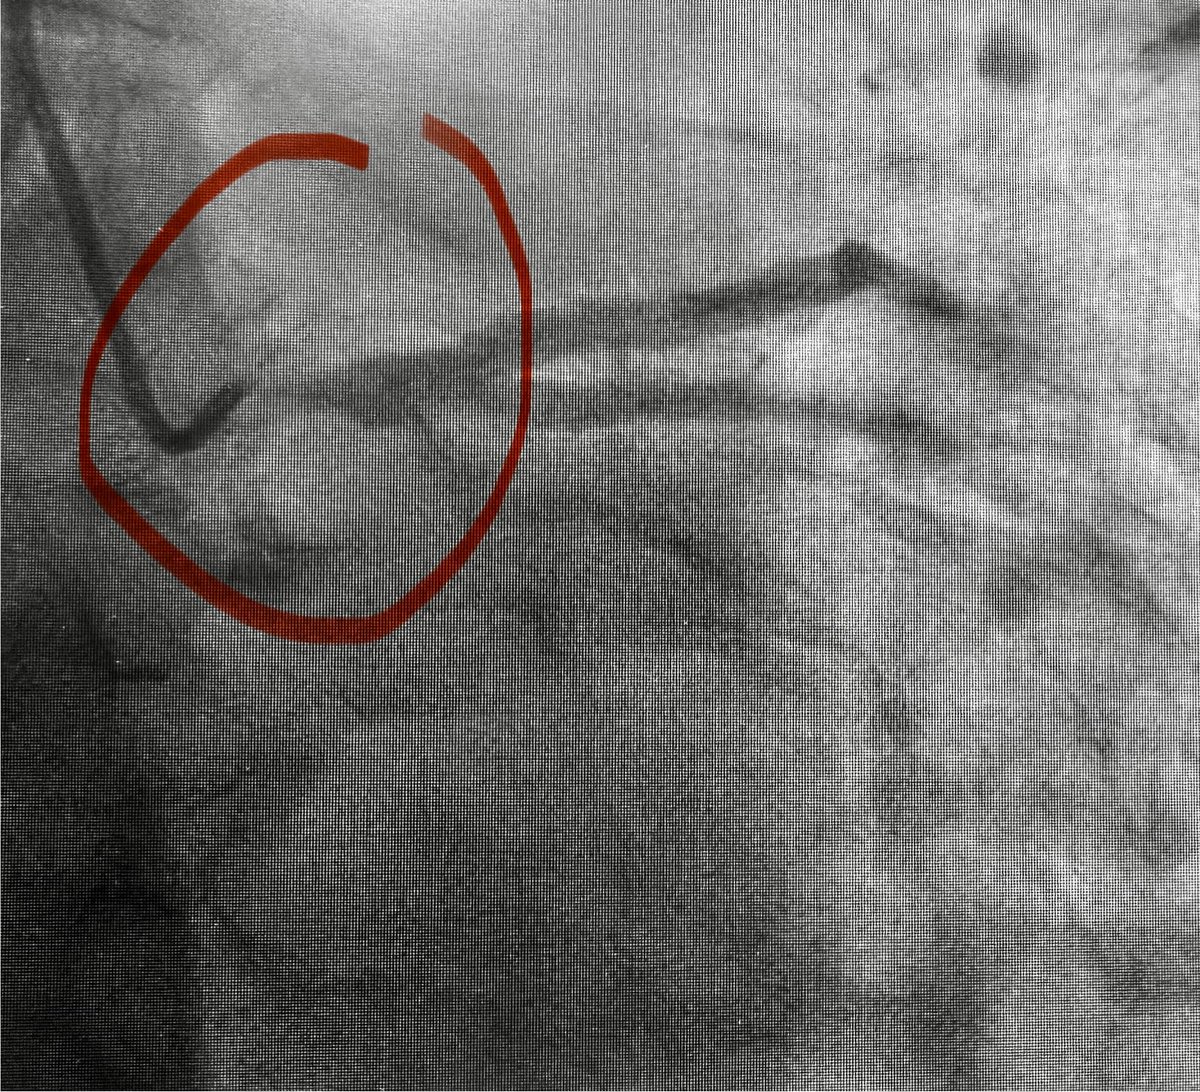

Introducing the percutaneous aorto-coronary bypass graft. The VECTOR procedure revascularizes the left main coronary artery using retrograde and antegrade steps: a retrograde wire exits the left main (distal graft), an electrosurgical wire exits the aortic root (proximal graft), a guidewire rail is created, and a stent graft is delivered from the aorta to the left main. What could possibly go wrong?

ahajournals.org/doi/10.1161/CI…